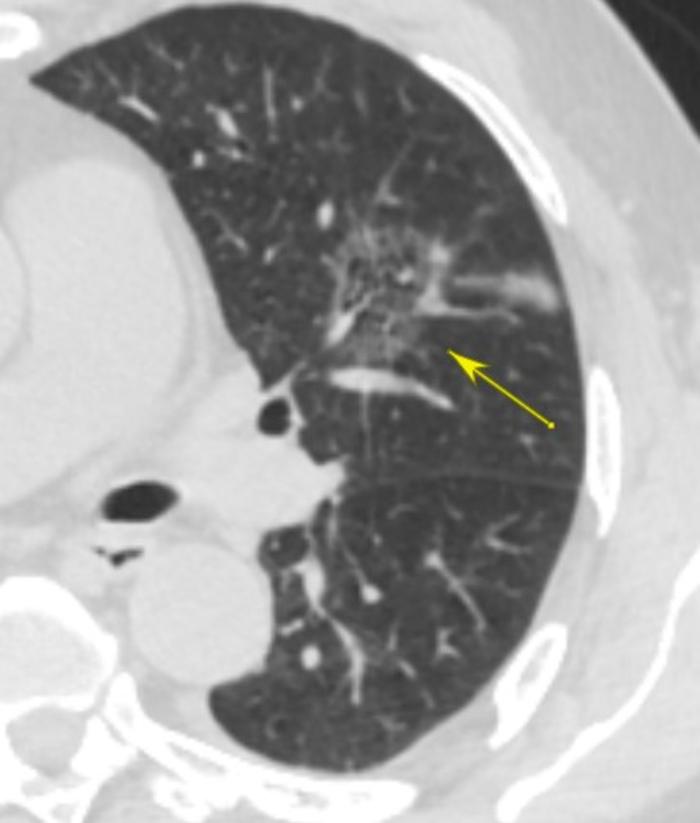

病例3:实性成分占绝大部分,边缘少许磨玻璃成分

箭头指示的是基本上是实性结节的左下角少许磨玻璃成分。黄色箭头的上方,可见结节与胸膜之间有胸膜牵拉征。

实性成分越多,恶性度越高。病理如下。

注意此患者病理也是浸润性腺癌。乳头型比例较高,占20%,恶性度较高。